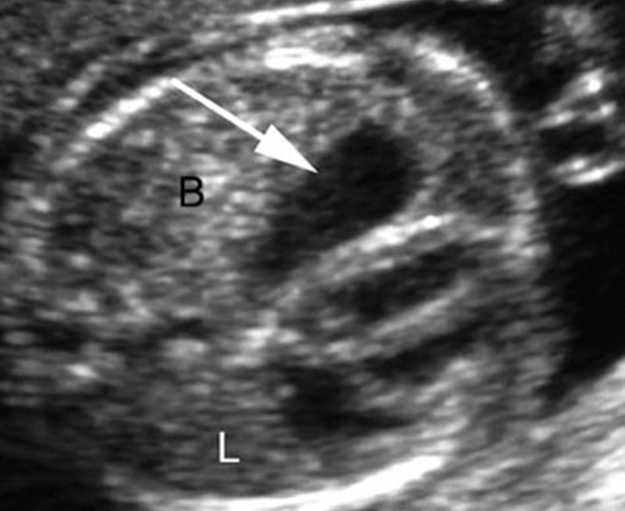

hydronephrosis